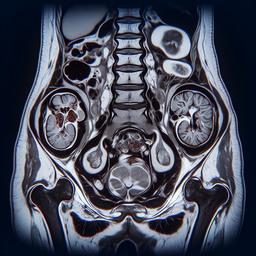

МРТ органів малого тазу

МРТ (магнітно-резонансна томографія) органів малого тазу – це високоточний неінвазивний метод діагностики, що використовує сильні магнітні поля та радіохвилі для отримання детальних зображень тканин і органів.